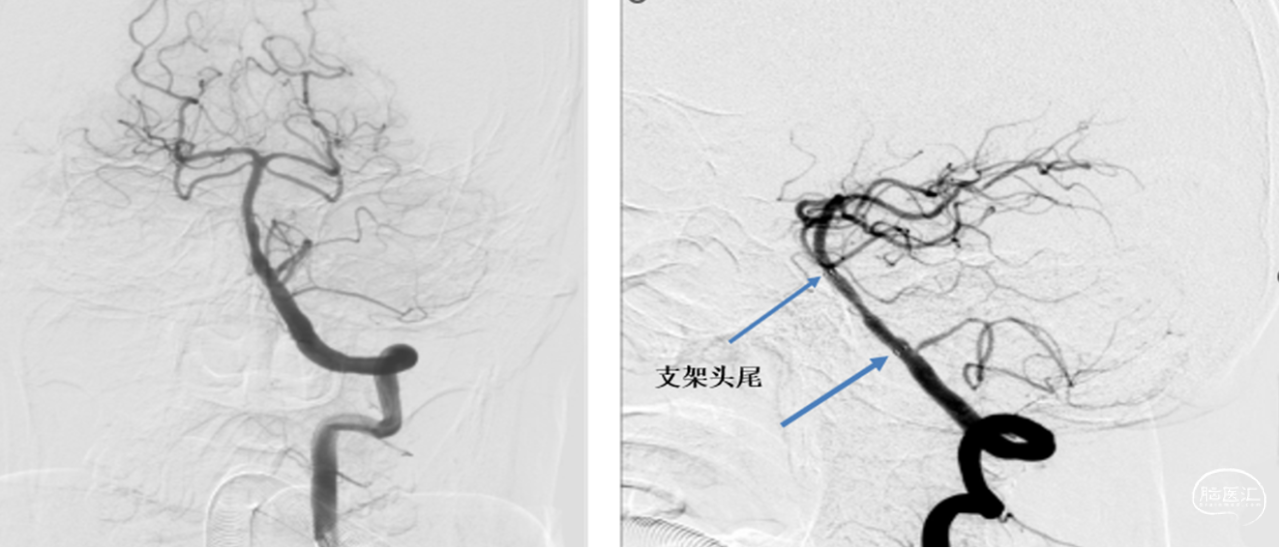

治疗过程

1、术中停用正在静脉泵入的替罗非班,予静脉肝素化(60u/kg, iv),肝素生理盐水稀释液持续冲洗导引导管。

2、0.035in导丝引导导引导管置于左侧椎动脉V2末端。

3、0.014in Synchro-2 soft 微导丝引导Echelon-10微导管置于左侧大脑后动脉P3段。

4、更换0.014in Floppy 300交换导丝,撤出微导管。

5、交换2.5*15mm球囊扩张导管,将球囊置于基底动脉狭窄处,缓慢充盈球囊至10ATM。

6、球囊完全泄压后回收,冒烟显示管腔狭窄解除。

支架植入:

1、选用Prowler Plus灌注微导管,沿交换导丝置于左侧P1段。

2、撤出微导丝,通过灌注微导管输送Enterprise-2支架,支架远端定位AICA(小脑下前动脉)开口近端,覆盖狭窄病变,释放支架后近端定位于左侧PICA开口远端(尽量不覆盖小脑后下动脉)。支架植入术后复查造影显示椎基底动脉狭窄解除。

操作技术要点:

1、基底动脉为富有穿支的血管,术中球囊扩张容易导致穿支血管闭塞。应用适合的球囊(血管直径的80%为宜)缓慢加压扩张至亚满意。

2、输送球囊时将微导丝小心到达相对粗大一侧的大脑后动脉P1远端,卸除导丝张力,保持微导丝固定不上窜,以防输送球囊时导丝前窜导致穿透血管出血。

3、支架植入铆定:上不覆盖小脑上动脉,下不覆盖小脑下前动脉等重要穿支血管。

4、椎动脉V4段狭窄支架植入铆定:上不覆盖小脑下前动脉,下部覆盖小脑后下动脉。